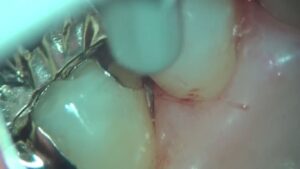

歯周病専門治療